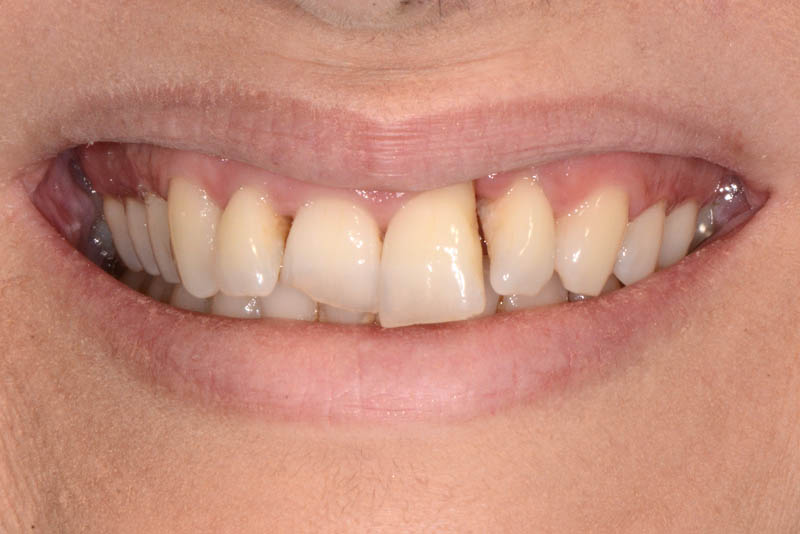

The healing has now reached a 5-year follow-up.

The patient is absolutely delighted with the outcome, but I have repeatedly (and unsuccessfully) encouraged her to undergo a small additional graft to address the minor residual recession on tooth 21.

I even offered to perform the graft free of charge, but she declined.

But then, is it really in the patient’s best interest to undergo another surgical procedure just to fulfill my personal desire for a perfect result?

Even if imperfect, I’m sharing this case.

It may not be suitable for a conference presentation,

but it was undoubtedly the best choice for the patient.